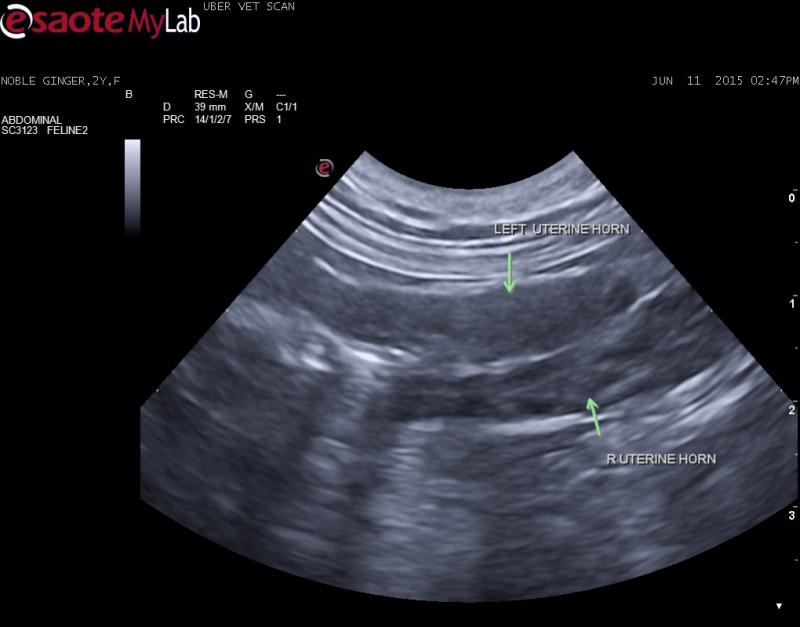

– u/s found no evidence of pyometra however the uterus is clearly visible, hypoechoic and one of the horns has a heterogenous appearance